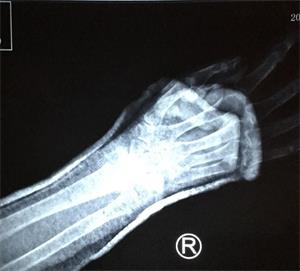

二月十三日,老人在积水潭医院复查拍片时,医生发现老人骨折处竟基本长愈,如图3。医生表示:老人家这个年纪了,一般都骨质疏松,半个月的时间,要想愈合到这种程度,就是年轻人,也是不容易的。并且说:老人的恢复情况确实很好。

'图3'

图3

老人及家人看到底片,都很开心,连说“没想到”、“真是奇迹”。